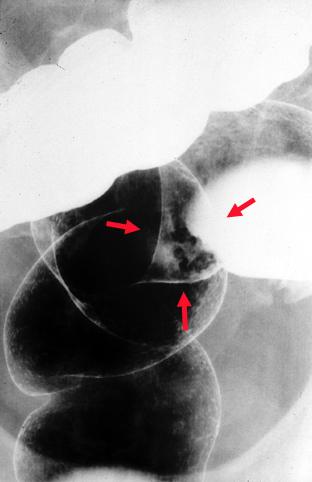

疾病(病理主体)的分类恶性上皮性肿瘤/腺癌

部位(按器官分)大肠/乙状结肠

检查方法X线

肿瘤的肉眼分类0型(表在型)/IIa型(IIa+IIc)

肿瘤最大直径10~14

肿瘤的深度sm